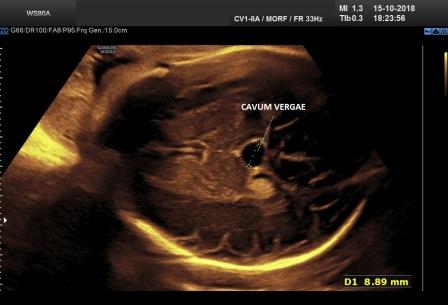

Cavum Vergae

Il cavo del

verga (cavum vergae) è l'estensione posteriore del cavo del setto pellucido nel

periodo fetale; lo si reperta al disotto dello splenio del corpo

calloso e in un 30% dei casi lo si può visualizzare anche nel periodo

neonatale.

Un cavo del verga di piccole dimensioni (< 10 mm.) è considerato fisiologico, mentre un cavo del Verga di diametro trasverso superiore ai 10 mm. (Tao et al. 2013 - Yoona et al. 2017) deve essere meritevole di ulteriori approfondimenti.